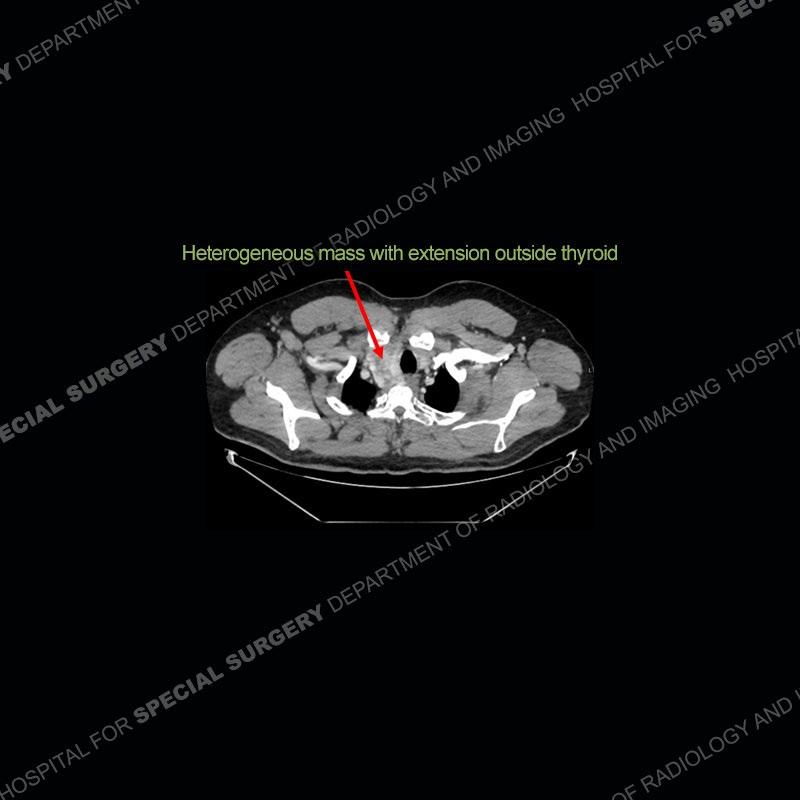

The chest radiographs demonstrate a leftward deviation of the trachea. CT images demonstrate a large, somewhat heterogeneous mass of the thyroid that extends outside the confines of the thyroid tissue. There is a subtle, enhancing soft tissue mass of the proximal right humerus. Slightly prominent mediastinal lymph nodes are present with additionally, multiple supraclavicular lymph nodes.

Over the years we have shown a couple of these cases which may be considered more so an “eye test” then anything else. In clinical practice, these are often very difficult cases as the initial finding of the tracheal deviation may be easily overlooked. Screening radiographs are clearly most often used to assess cardiopulmonary function before induction of anesthesia but at times other findings of great and unfortunately grave consequence can be found. The evaluation of the incidental thyroid mass on CT and MRI is an ever changing situation. Parameters such as age of patient, extension outside of the thyroid, enhancing nodules, and local invasion of lymph nodes are evaluated to see if a lesion needs to be further evaluated.

Although not strictly a part of the evaluation of an “incidental” thyroid lesion, evaluation of the adjacent lymph nodes and bony structures can also be quite important. In this case, there is an enhancing mass of the right humerus. This is very subtle and can only really be recognized by evaluating the density of the bone. Typicaly marrow will have a fatty density or nearly fluid density. As the density, as in this case, approaches soft tissue an infiltrative process must be entertained. Thyroid mets are markedly vascular accounting for the areas of enhancement of the humeral mass. The mediastinal and supraclavicular lymph nodes although not individually enlarged, should raise suspicion of an underlying inflammatory/neoplastic process.